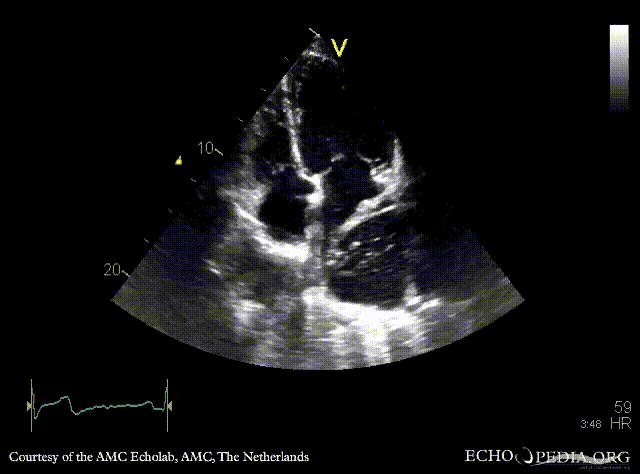

| PLAX: large cyst adjacent to left atrium, compression of LA | PSAX |